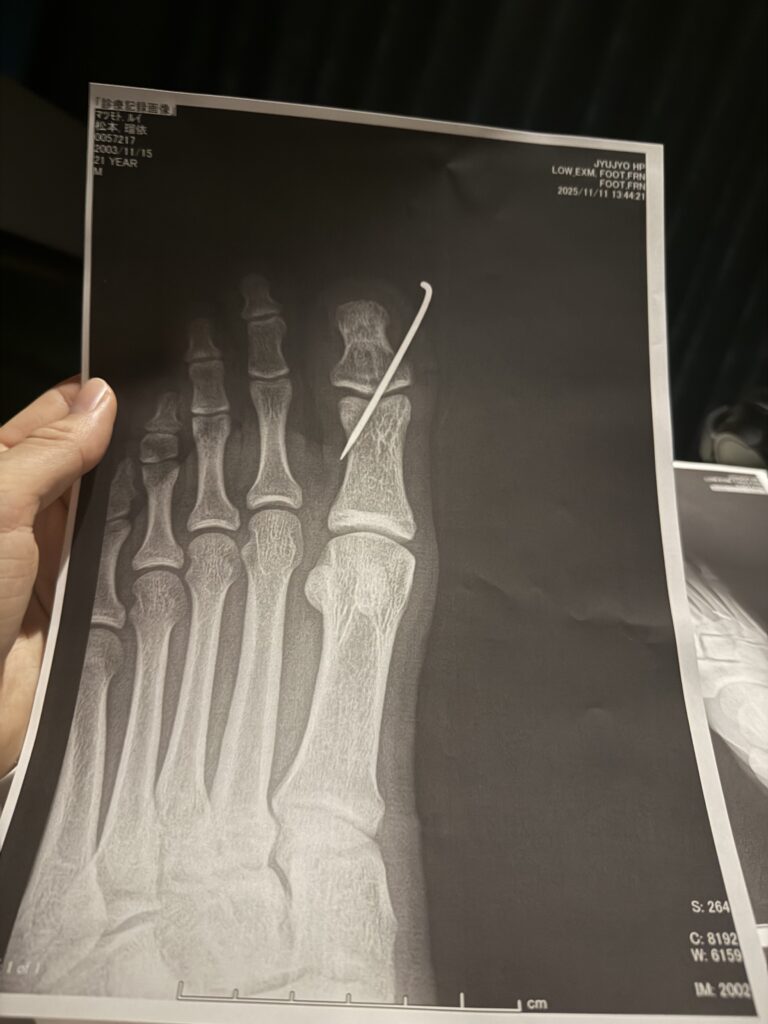

先日の試合にて足を骨折してしまい、しばらくの間インストラクター業務が難しい状況となってしまいました。自分自身とても悔しい気持ちでいっぱいですが、まずはしっかり治し、必ず復帰して皆様の前に戻ってきたいと思っています。